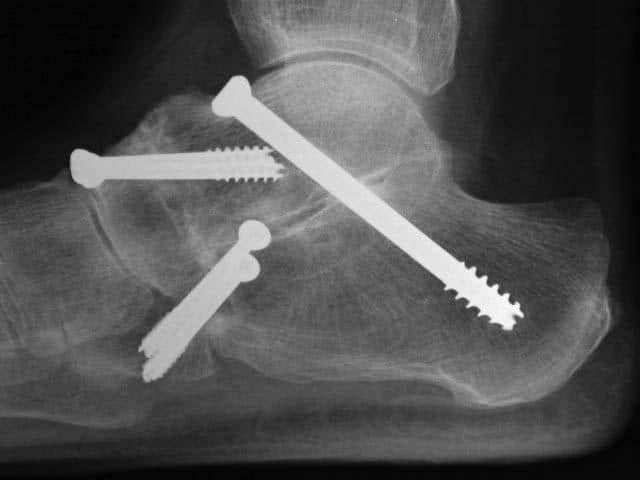

To improve the biomechanics of the tendon transfer the heel bone is moved towards the inside of the foot (calcaneal osteotomy) and held with screw fixation. In addition, a plug may is inserted into the outer portion of the foot to assist in supporting the arch. If required the plug and/or screws can be removed in a second operation when they have served their purpose and the tendon is healed. Additional procedures such as synthetic tissue augments, lengthening of the achilles tendon and other bony surgery may be required and will be discussed if thought necessary.

In more advanced cases, up to three of the joints in the foot can become arthritic. These joints (subtalar, talo-navicular, and calcaneo-cuboid) are fused using bone graft taken from nearby bone or from processed bone bank bone. This is known as a triple fusion.